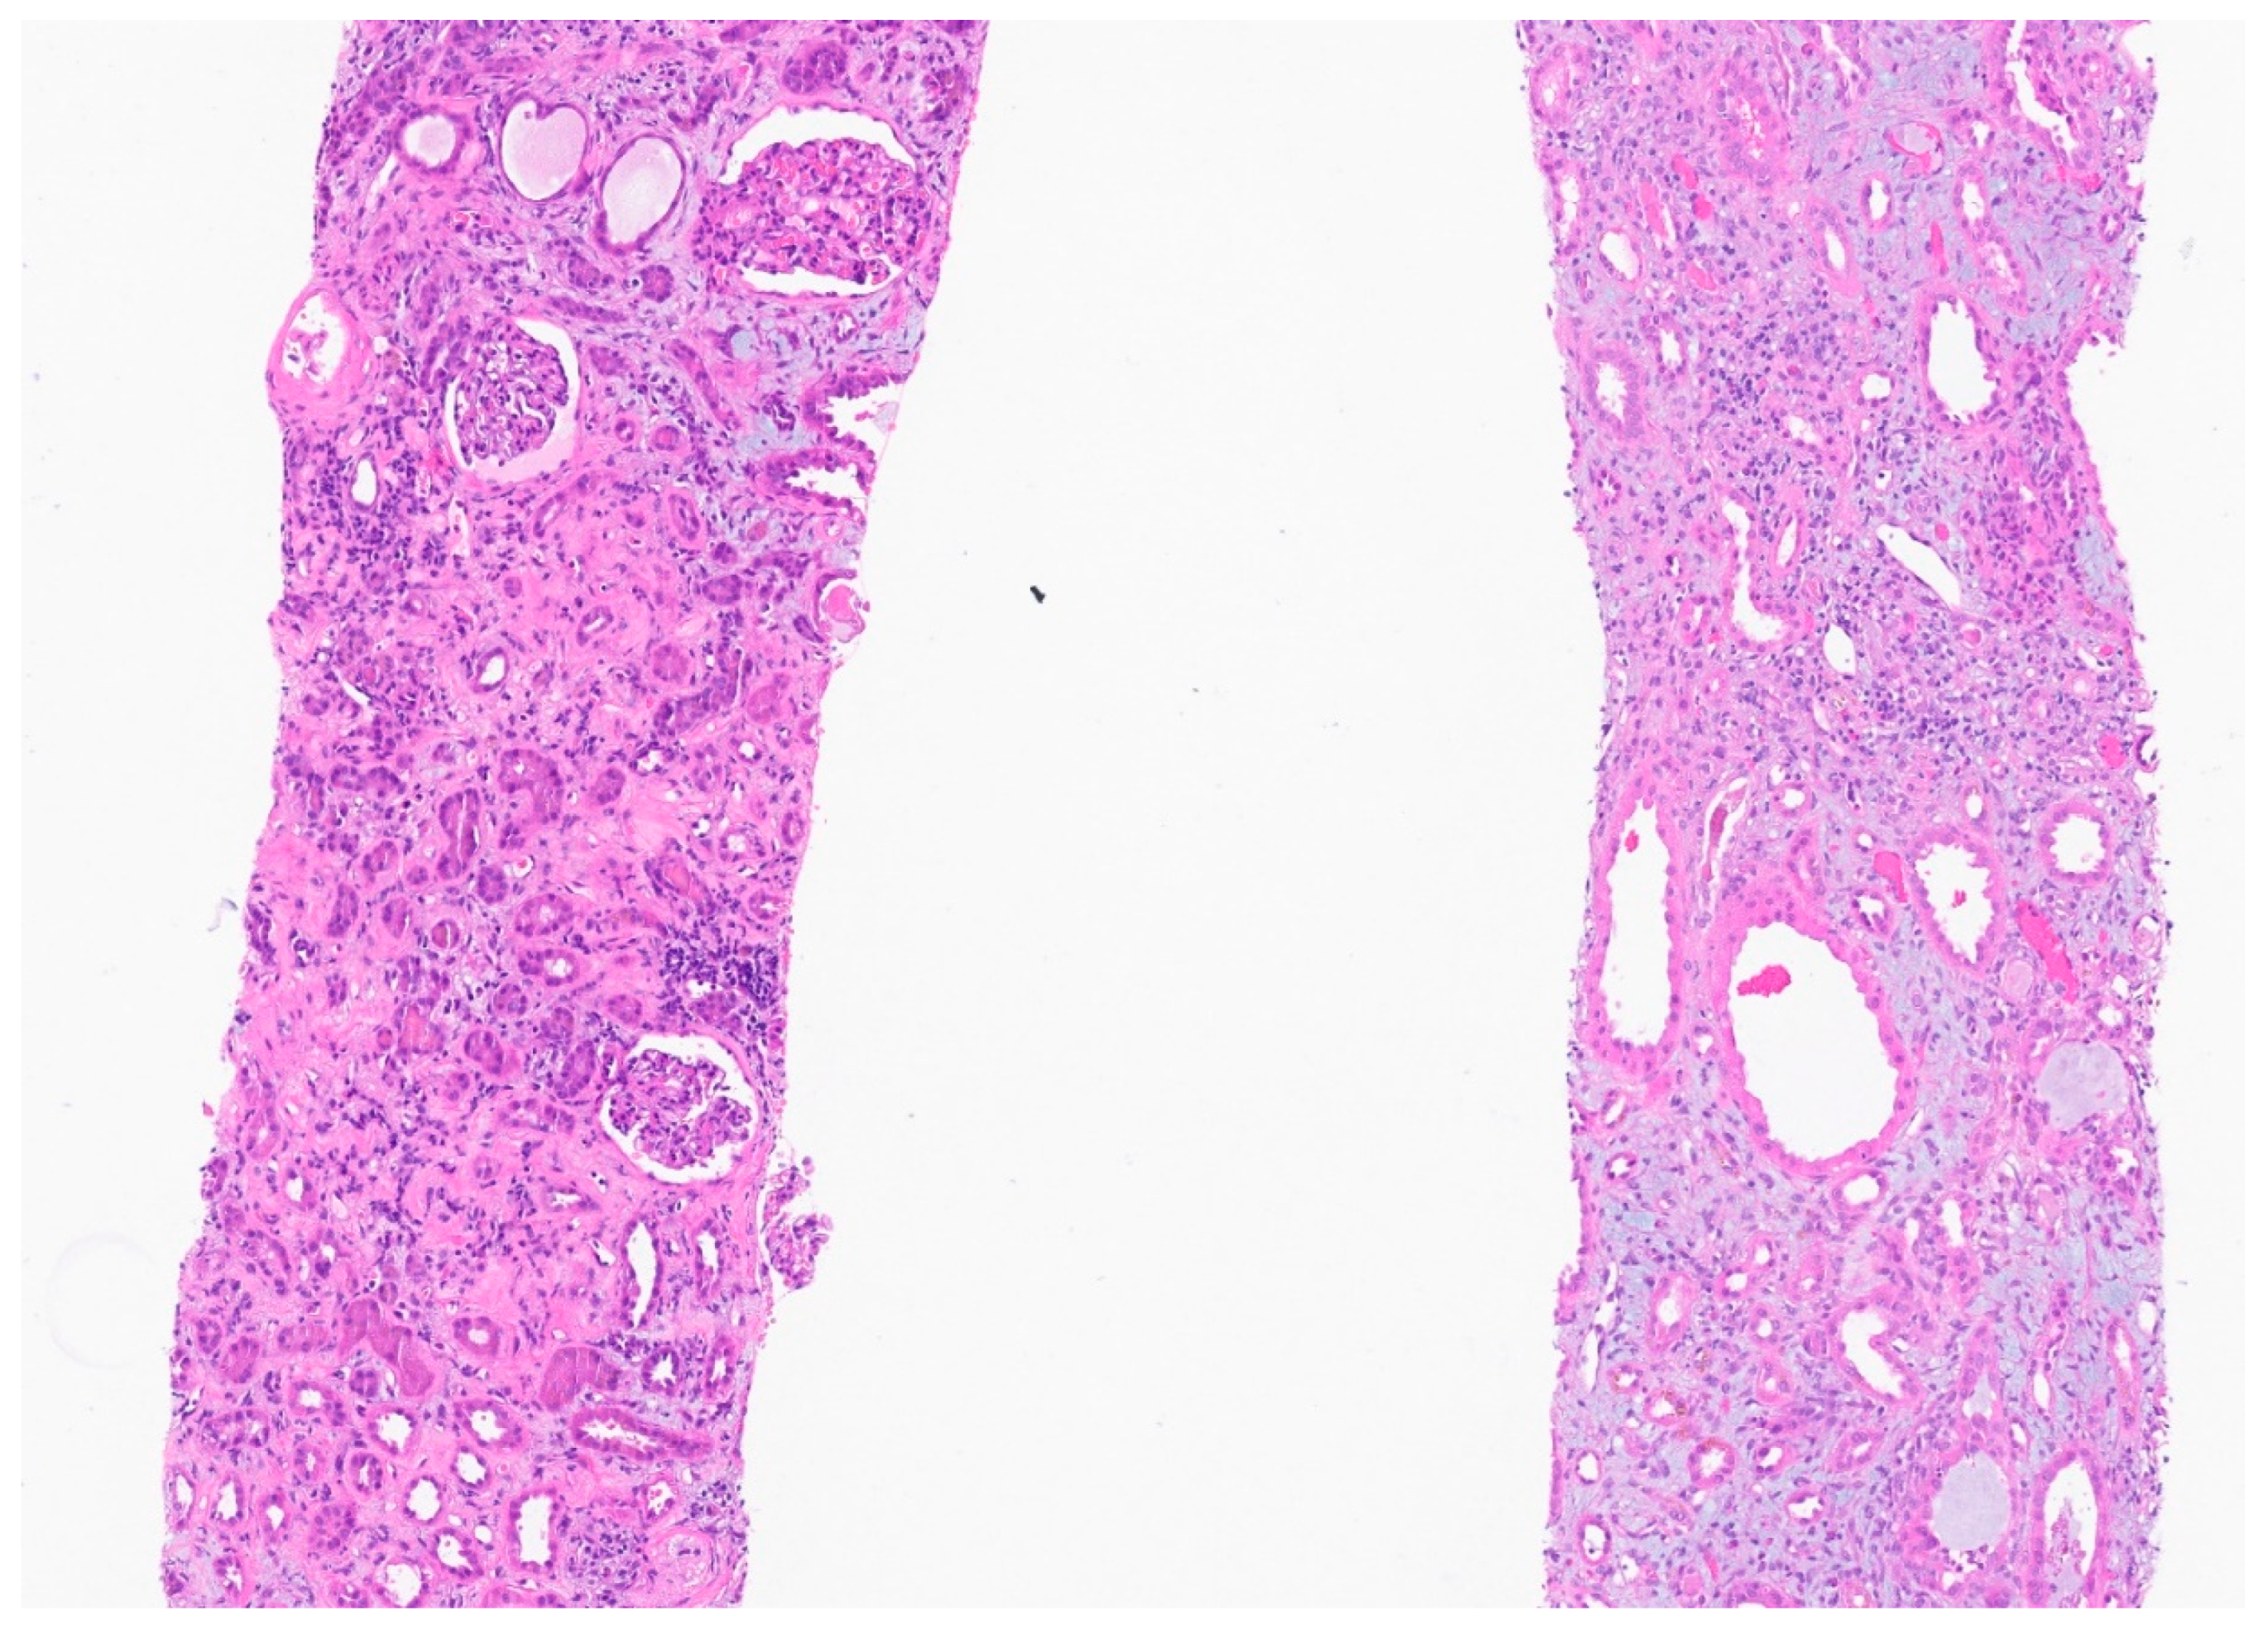

Figure 1. There is edema and marked diffuse mononuclear tubulointerstitial inflammation. The tubules have simplified epithelium with lost brush border and reactive nuclear changes. There is no significant tubular vacuolization. The glomeruli appear spared.

TUBULES AND INTERSTITIUM: There is severe diffuse interstitial edema involving cortex and medulla. There is severe tubular epithelial cell injury with luminal ectasia, fraying of the brush border, and simplification of the lining epithelium. Tubular lumina contain necrotic debris, and some lumina contain hyper eosinophilic ropy casts. The interstitium contains dense infiltrates of lymphocytes. Some areas contain aggregates of eosinophils. Mild tubulitis is seen. There are intratubular oxalate crystals (at least 3).

Electron Microscopy: Normal cellularity and mildly expanded mesangial regions are confirmed. No immune complex or paraprotein-related deposits are seen, and the glomerular basement membranes show wrinkling of several of the segments, but otherwise show no ultrastructural abnormalities. There is mild foot process effacement present. Examination of the tubulointerstitial compartment shows interstitial edema, severe interstitial inflammation, and multifocal tubulitis. No tubular basement membrane deposits are seen.